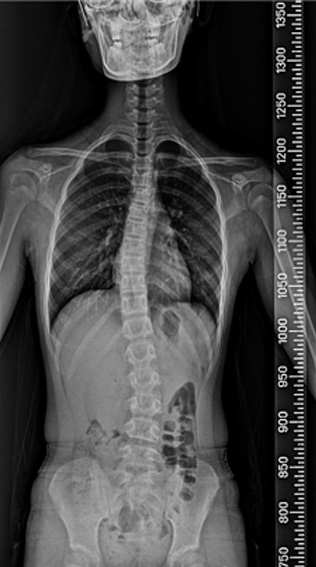

척추 측만증은 80%가 사춘기 때 발생하며, 사춘기 여아의 10~14%, 사춘기 남아의 5%에서 나타나는 것으로 알려져 있습니다. 성조숙증이 있는 아이들은 더 어린 나이에 급성장이 온 것이기 때문에 척추 측만증이 생길 가능성이 더 높습니다. 성장호르몬 치료를 하는 경우에도 사춘기때처럼 급성장을 하기 때문에 척추 측만증이 생길 가능성이 더 높습니다. 물론 이는 약물 부장용이 아닌, 일종의 성장 부작용인 셈입니다. 척추 측만증은 심할수록, 골연령이 어릴수록, 그리고 역연령이 어릴수록 점점 더 심해질 가능성이 높으며, 따라서 가능하면 조기에 발견하여 치료하는 것이 좋습니다. (from Lonstein & Carlson) 이렇게 척추 측만증은 일종의 성장기 합병증으로 볼 수 있으며, 따라서 성장판이 닫칠 때까지 더 진행될 확률이 높고 대신 성장판이 닫치면 진행도 멈추게 됩니다.

척추 측만증 : 앉아 있기가 힘이 들며 어깨 높이가 다른등 척추 부위 통증 및 걸음걸이, 자세등에 다양한 불편감 호소.